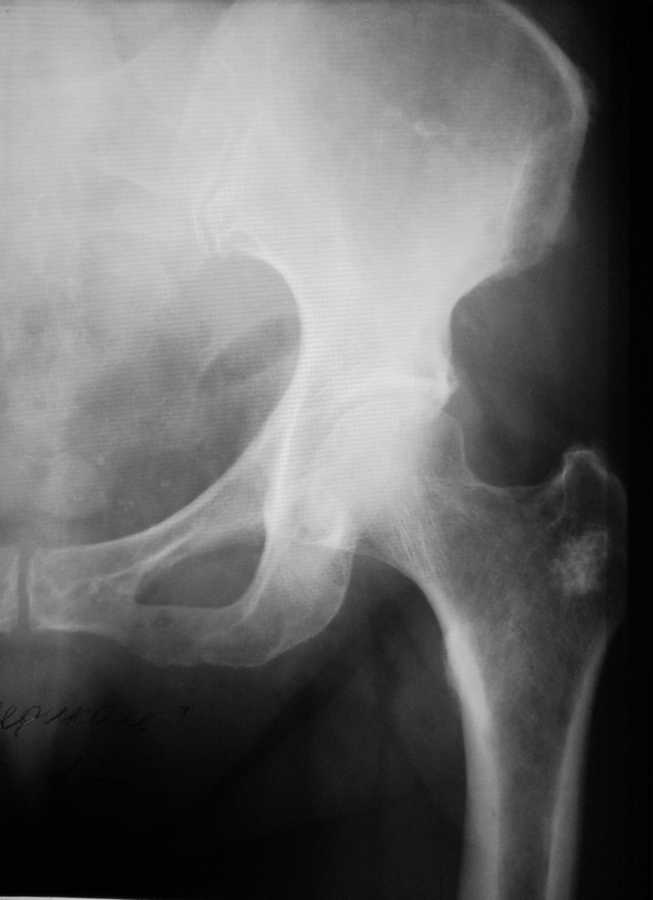

Уважаемые коллеги! Прошу Вас помощи по поводу ситуации, представленной на снимке левого Т/Б сустава. Пациентка 65 лет, рост около 165, вес около 90кг.Клинически боли в суставе при ходьбе.При пальпации болезненность в области вертела. Пассивные движения в суставе в полном объеме, безболезненны.

1. Это рентгенконтрастное новообразование (далее НО), ок.1.5-2 см, которое поразило большой вертел бедра женщины 65-ти лет, рост... вес... и через это она (женщина) испытывает боли при ходьбе и когда ей вертел пальпируют.

2. Жалобы с суставом не связаны.

4. По снимку не совсем ясно, есть ли зона лизиса вокруг НО? а следом за ней нет ли ободка склероза? Нет ли изменений в кортикале, истончение, прорыв, периостальных реакций?

Желательно сделать КТ, конечно.

Может оказаться вторичной хондроSa. Сделайте КТ,МРТ.

множественная миело